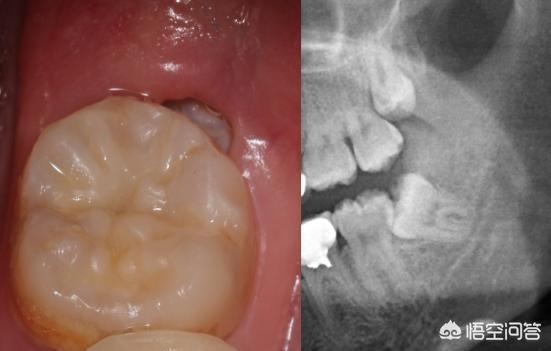

翌日、顔の半分が腫れ上がり、病院に行くことになった。病院で診察を受けた結果、親知らずが炎症を起こしており、むし歯になっていると言われた。

医師は、親知らずの抜歯と虫歯の充填を勧めた。詰め物は、結局のところ、真ん中が空っぽになり始めているのを受け入れました。しかし、私は歯を抜くことを拒否した、それは少し怖いように見えるし、歯がなくなっている。